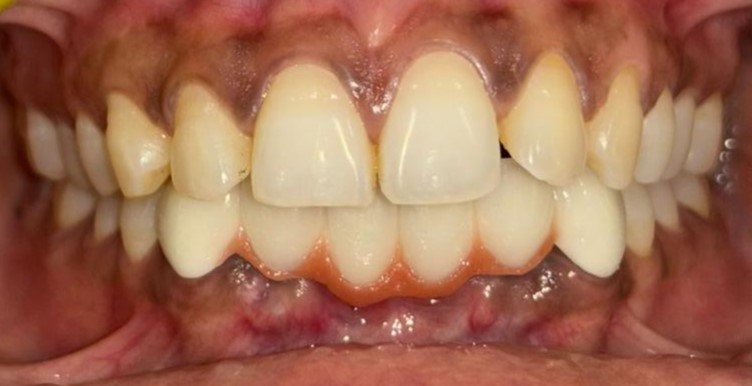

After After

Before Before